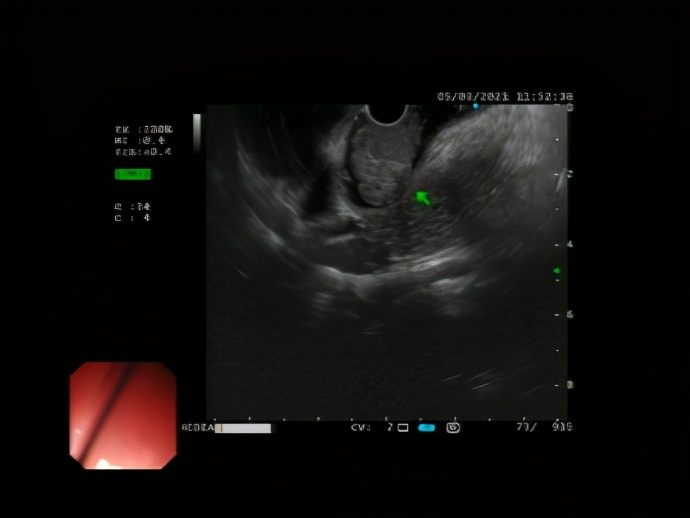

在南方医科大学南方医院帮扶专家、我院副院长兼消化内科学科带头人李跃副主任医师带领下,消化内科诊疗团队高效率运转,完成术前检查及术前评估,在许女士入院第二天完善超声内镜检查,并在 内镜下行肿物切除术, 大小约4.0x2.5cm,术中出血0ml。

△ 超声胃镜提示十二指肠粘膜下层来源肿物